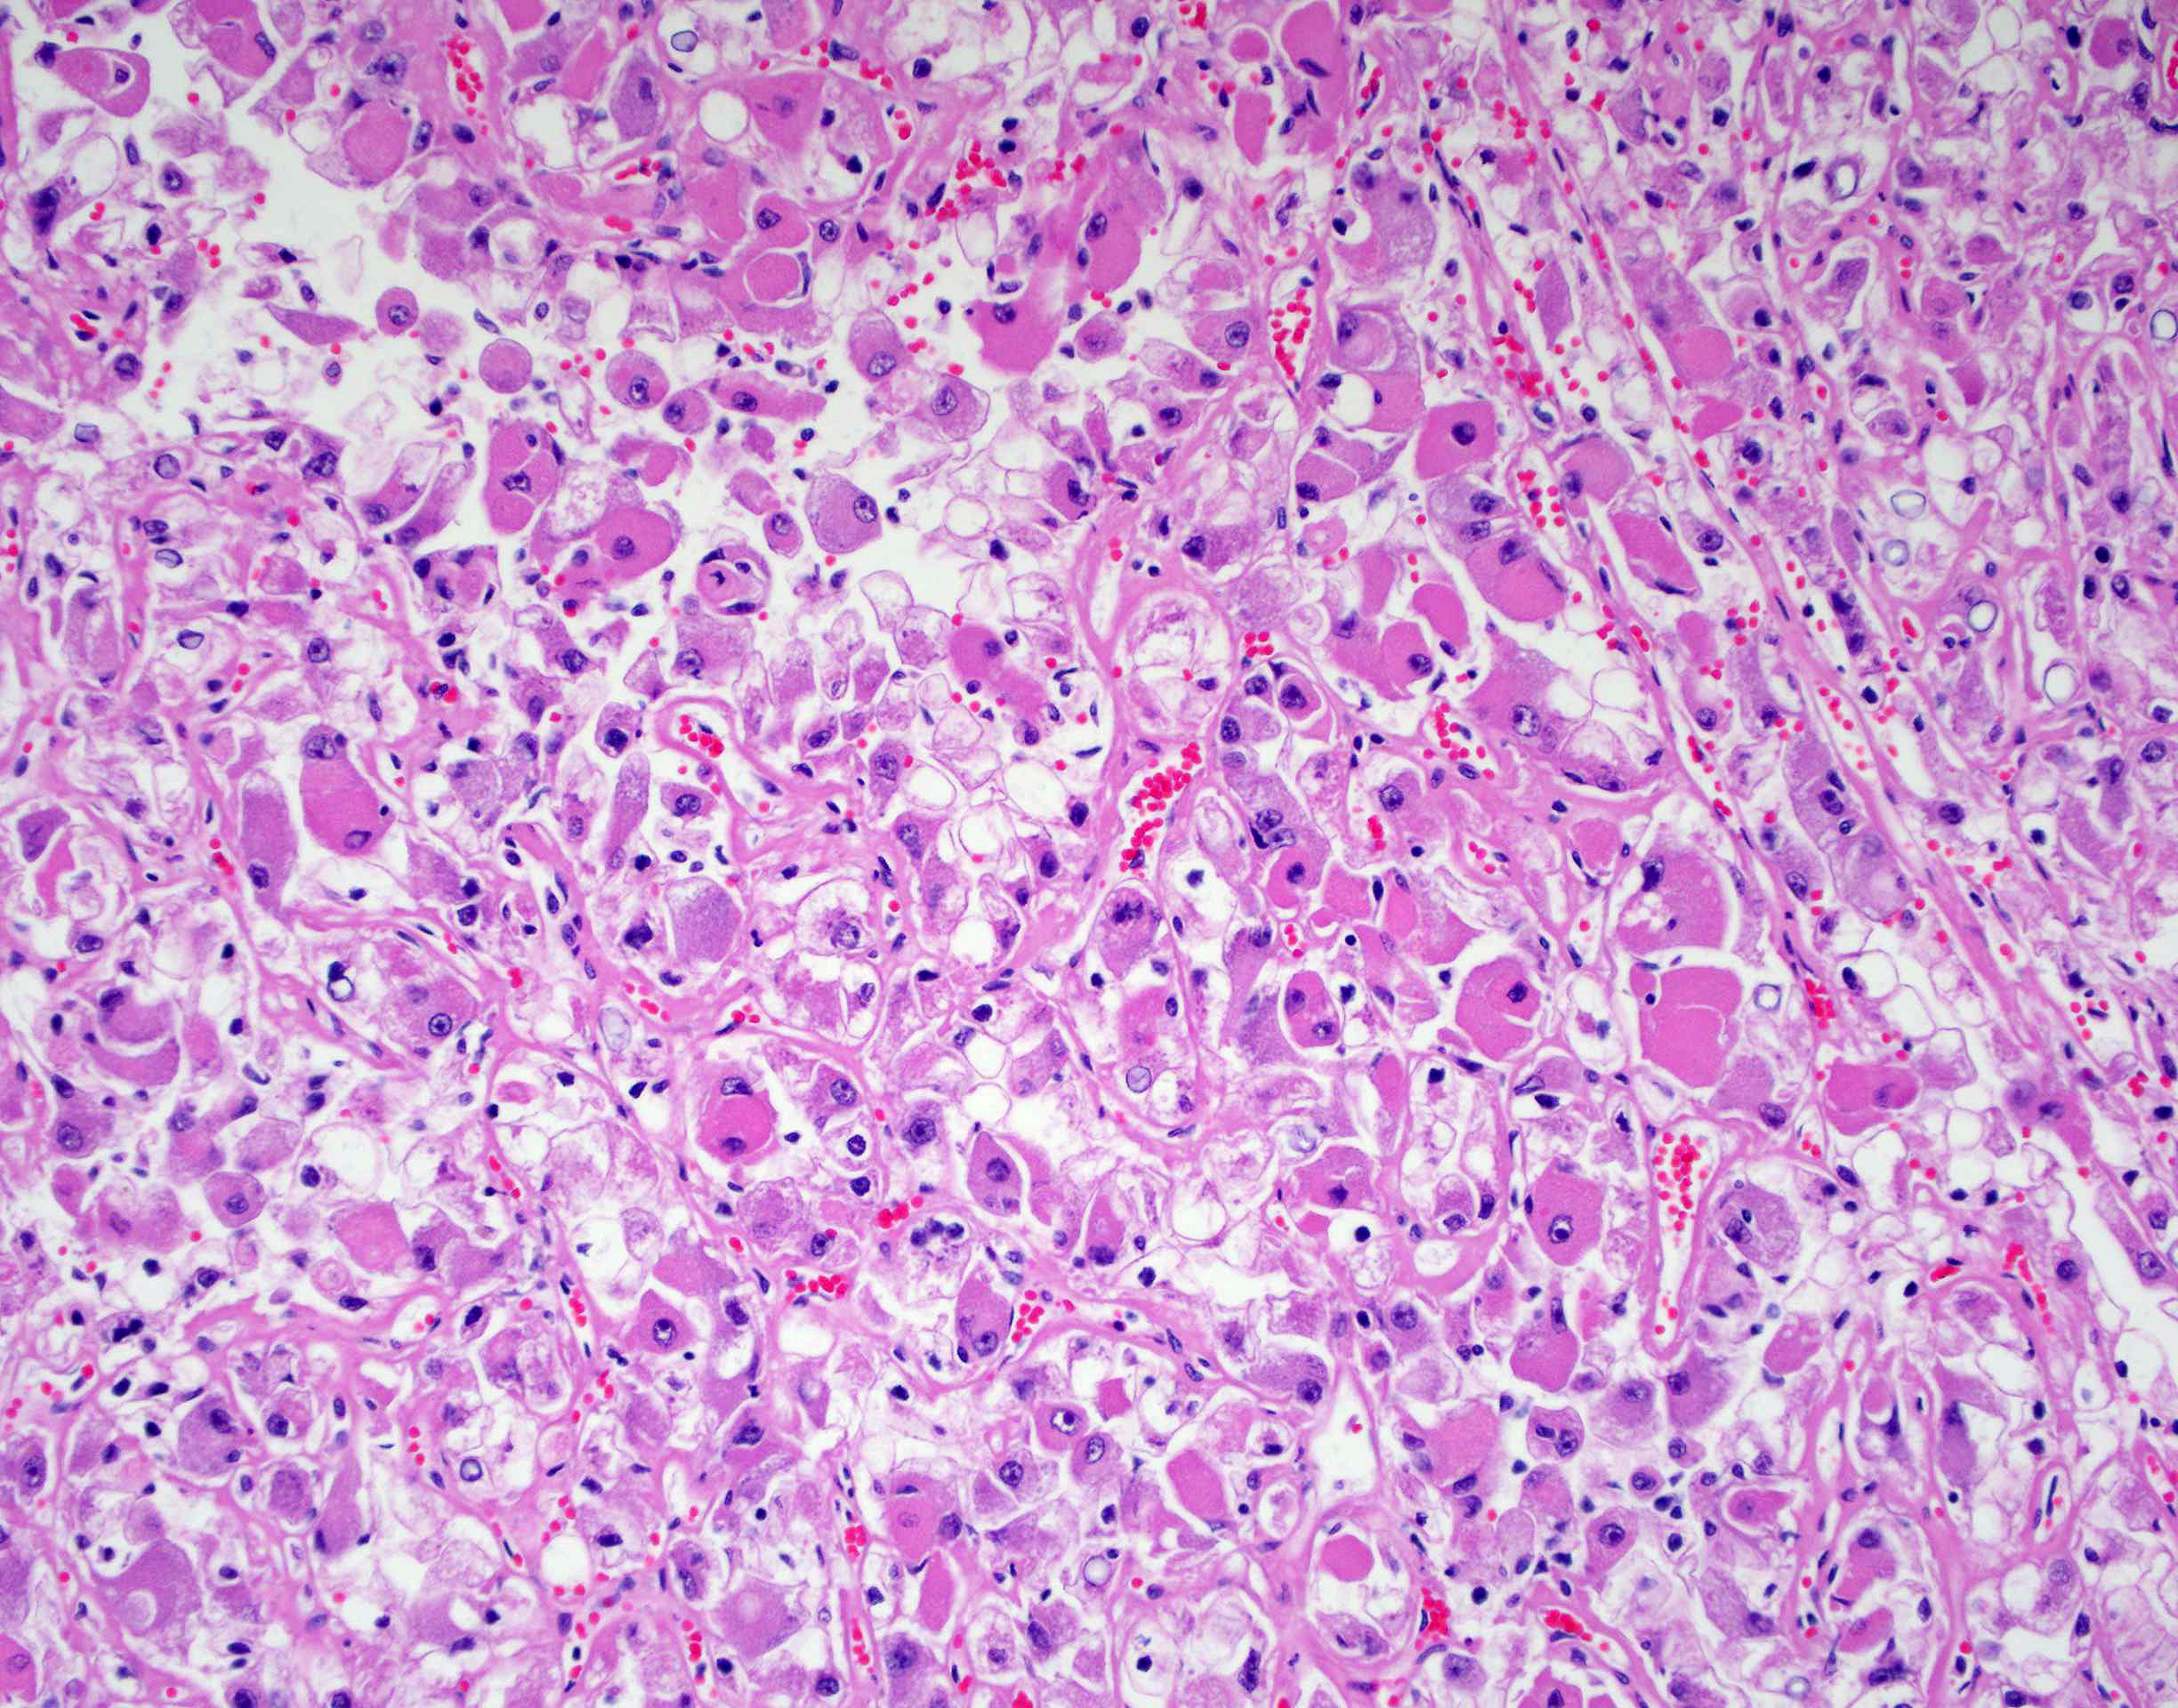

Renal tumor grading

Case ID: 419